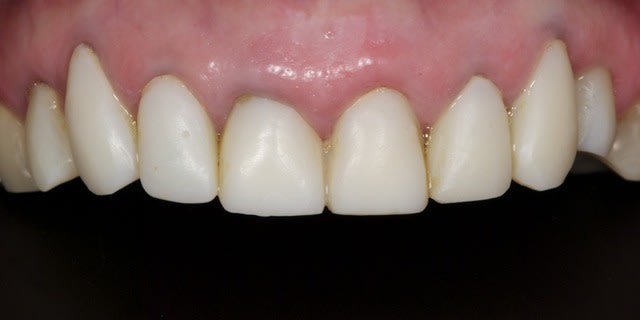

La suite avec les deuxièmes provisoires en places, le projet esthétique étant validé, les emp. ont été réalisées, ceramo-metal sur moignon composite a venir..

08/03/2013 à 00h21

Bravo,

Très beau cas.

Une photo des préparations aurait été utile pour comprendre le choix des matériaux pour les CCM ou CCC.

Notamment pour la 21 qui me semble un peu grise avec la provisoire sur l'angle mésio vestibulaire.